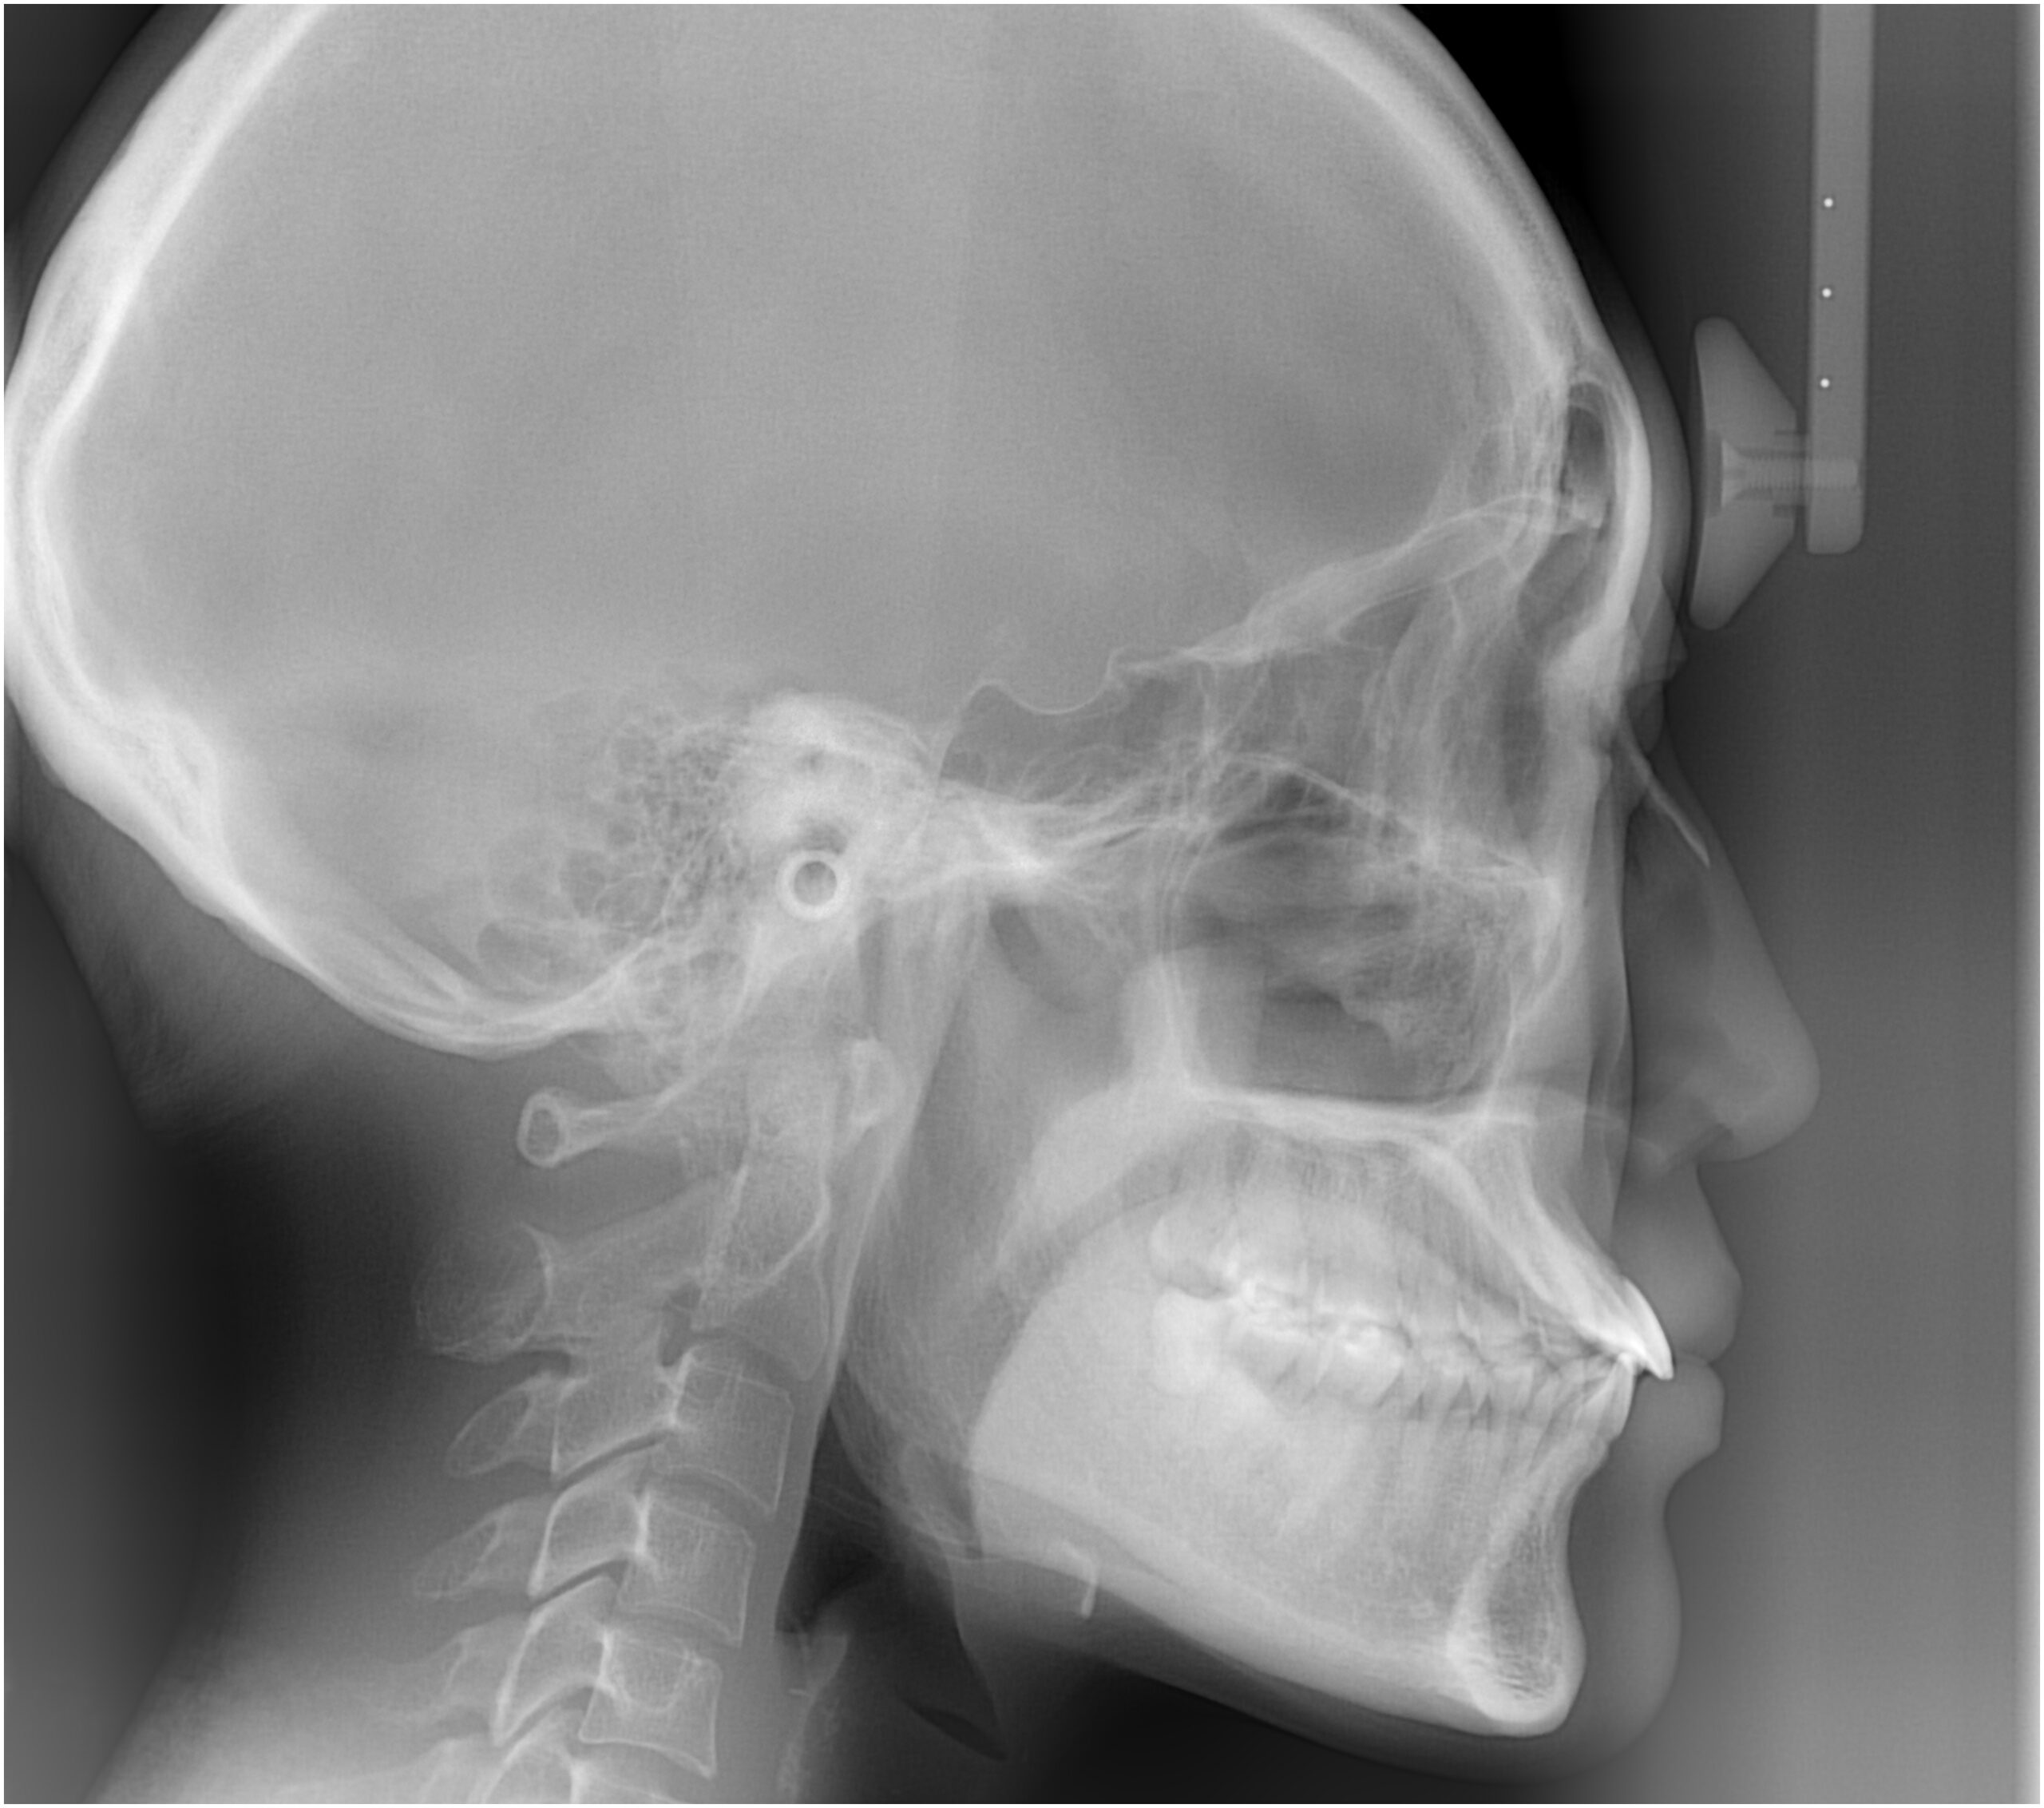

セファログラムのトレースの重ね合わせ(緑:治療前、赤:治療終了時)

![]() |

治療前後の解説

| 治療後 | 前歯から奥歯まで全体的に緊密な咬み合わせになっています。 治療前後のセファログラムのトレースの重ね合わせを比較すると、上下の歯列の後方移動ができ、それにより口元もよりすっきりしました。 また前歯の唇側傾斜も改善されています。 |